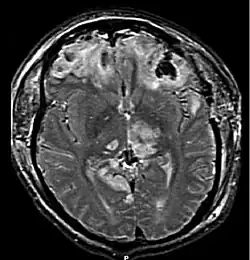

| MRI showing injury due to brain herniation | |

Brain herniation is a potentially deadly side effect of very high pressure within the skull that occurs when a part of the brain is squeezed across structures within the skull. The brain can shift across such structures as the falx cerebri, the tentorium cerebelli, and even through the foramen magnum (the hole in the base of the skull through which the spinal cord connects with the brain). Herniation can be caused by a number of factors that cause a mass effect and increase intracranial pressure (ICP): these include traumatic brain injury, intracranial hemorrhage, or brain tumor.[1]